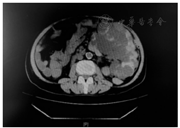

6个月前,受者以"高热伴左侧腰痛、恶心呕吐6日"入院,体温最高39.5 ℃,给予哌拉西林钠/他唑巴坦钠4.5 g/d经验性抗感染治疗,血培养提示大肠埃希菌(+),腹部CT检查(图1)显示,左肾明显增大,左肾实质内可见多发大小不等的类圆形低密度灶,内可见散在结节状致密高密度灶,考虑左侧多囊肾囊内破裂继发感染,调整抗生素为美罗培南2 g/d,并行左肾切除术,术后受者体温恢复正常,血肌酐稳定(波动在129~156 μmol/L)。